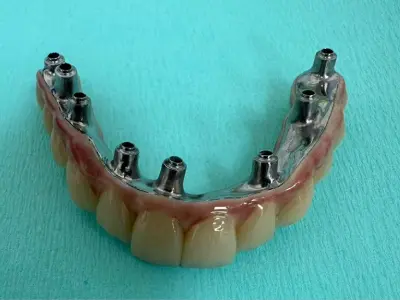

שיקום לסת שלמה באמצעות גשר נתמך שתלים

4 שתלים לעיגון תותבת